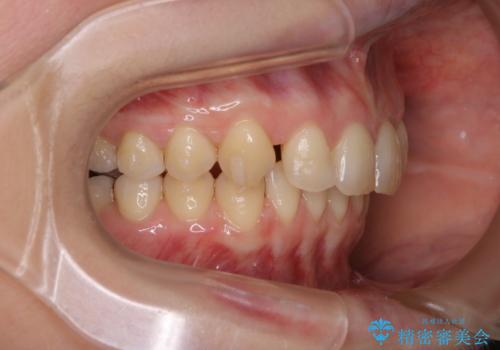

- 着色を落としてほしいとのことで来院されました。

PMTC60分コースを行いました。

着色がとても多くついていました。着色がここまでついていると、目立ちますし、マウスピースをはめたままのお水以外は飲むのは控えましょう。